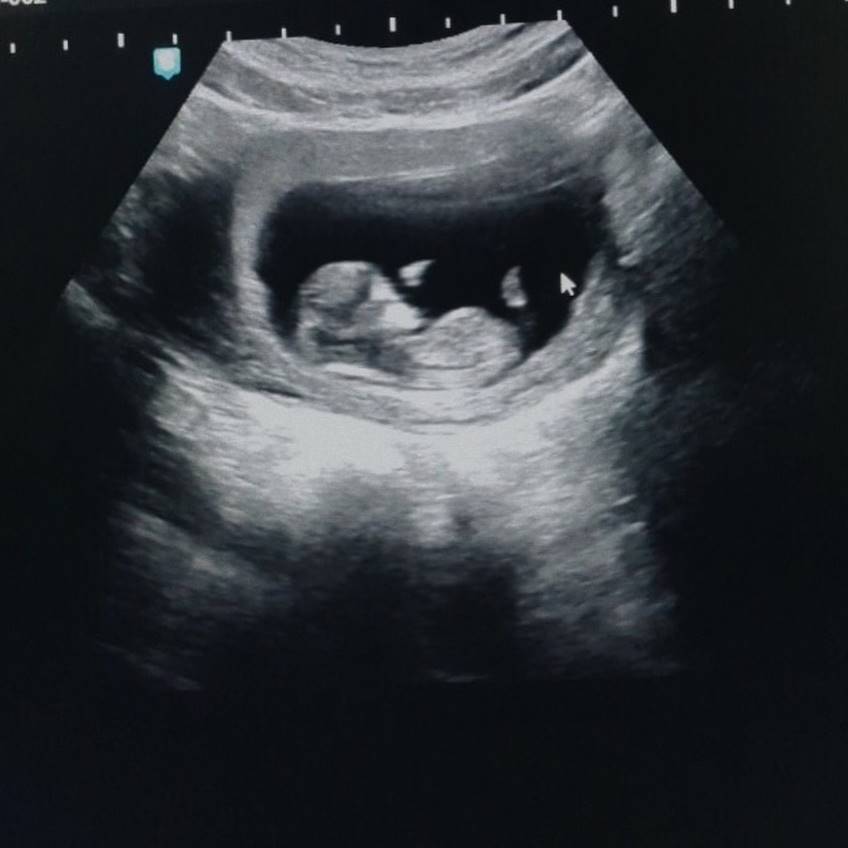

2. Hamil 4 Bulan

Saat ini usia kandungan fashion stylist itu rupanya juga telah memasuki usia 4 bulan. Selamat buat Haykal dan Tantri!

Saat itu, keduanya pun pergi ke dokter dan akhirnya mendapatkan kabar bahagia bahwa Tantri tengah hamil satu bulan.